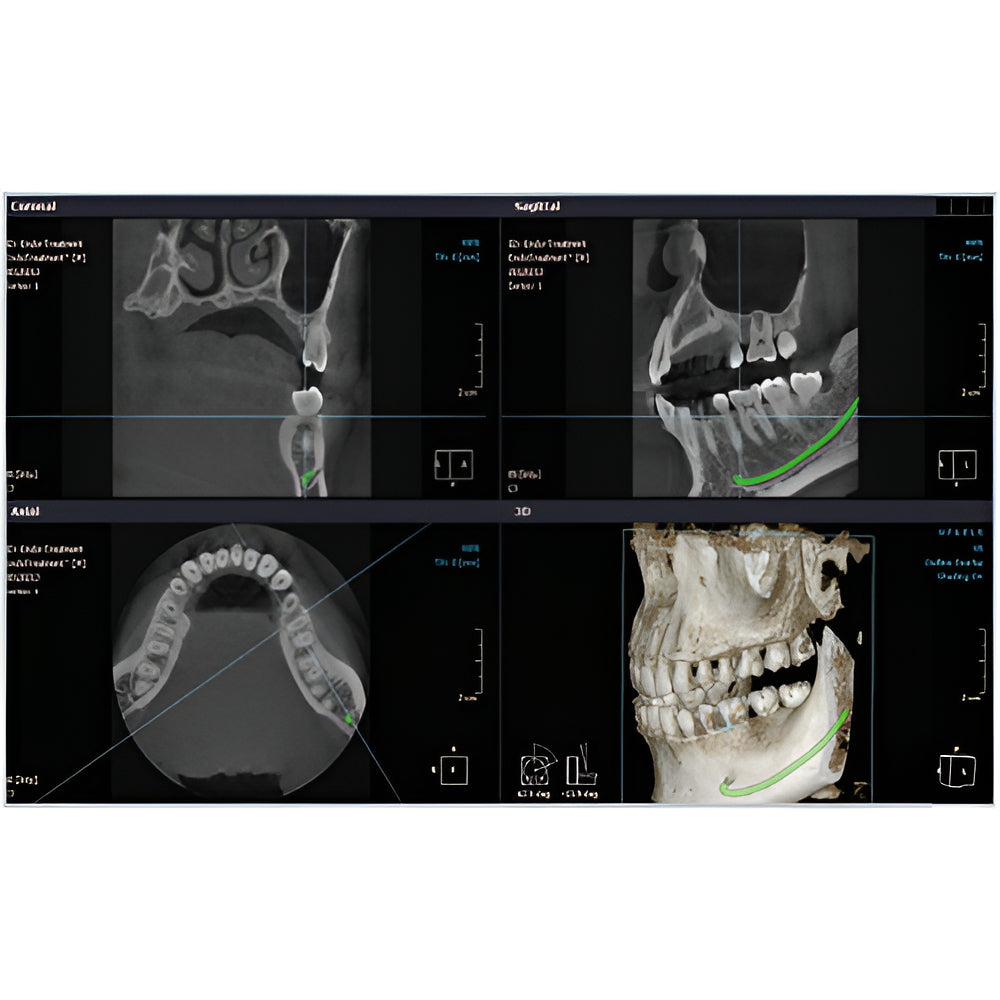

Rayscan Alpha brings another innovative technology with less Recon time and bigger FOV Size. And there are also new features – Fast scan mode, Object scan and Multi FOV.

- 2D/3D Imaging Software with License

- Panoramic

- Cephalometric

- Quick Scan Times

- Multiple Scan Modes